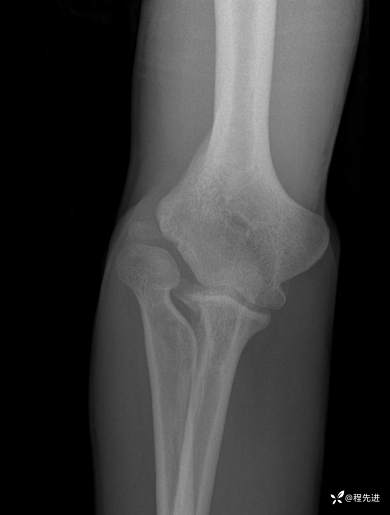

右肘关节正侧位DR:

img